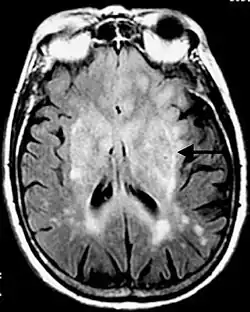

Cechuje się rozplemem atypowych astrocytów w różnych strukturach mózgowia. W tomografii komputerowej daje obraz rozsianych ognisk hipodensyjnych, guz rzadko daje efekt masy (niekiedy stwierdza się asymetryczne zaciśnięcie bruzd mózgu na sklepistości)[2]. Bardziej czułym badaniem jest MRI, w obrazach T2-zależnych glejakowatość mózgu daje obraz mnogich hiperintensywnych ognisk. Charakterystyczne jest objęcie przez proces rozrostowy więcej niż dwóch płatów mózgu[3]. Rokowanie na ogół jest złe. Glejakowatość mózgu została opisana przez Samuela Nevina w 1938 roku[4].